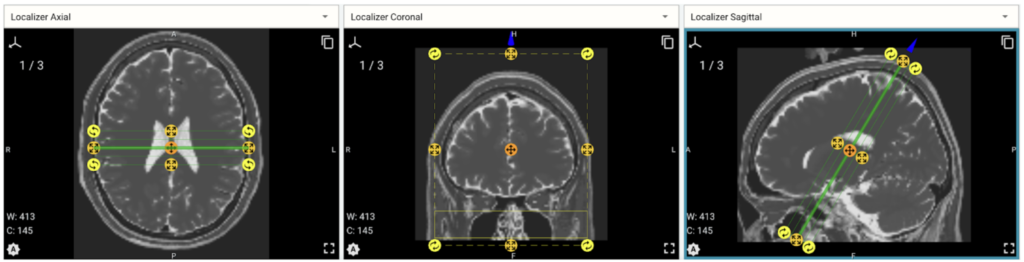

This project was about fixing a mismatch between the orientation of MRI slices before being processed by a Python engine and after that processing.

I fixed the problem and delivered a fixed Python program along with a document that explains the solution.